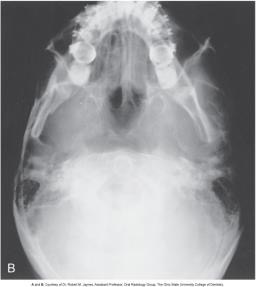

Submentovertex

purpose for submentovertex

used to identify the position of the condoles; used for zygomatic fractures